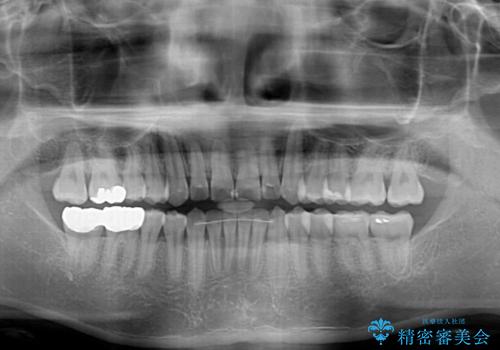

- 右下奥歯の虫歯がしみて痛いとのことで来院された患者様です。

神経近くにまで及ぶ大きな虫歯でしたが、速やかに処置を行い、痛みは即日解消されました。

虫歯が大きかったため、クラウンによる補綴治療が必要になる旨をお伝えしたところ、矯正治療にも興味があるとのことでした。

短期間で手間のかからない方法がご希望でしたので、ワイヤー装置による矯正治療を行うこととし、矯正治療後に右奥2歯をセラミッククラウンにて補綴することとしました。

セラミッククラウンによる補綴治療と矯正治療の双方が必要となる場合、矯正治療前の処置や歯の移動中に必要な処置など、二種類の治療を同時にチェックすることがとても重要となります。